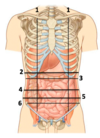

Name those lines

- Midclavicular (or midinguinal) line

- Transpyloric plane

- Subcostal plane

- Transumbilical plane

- Intertubercular plane

- Interspinous plane

Name these

Name the content of the 4 quadrants

Right upper quadrant

Liver and Gallbladder

Left upper quadrant

Stomach and spleen

Right lower quadrant

Cecum, appendix, ascending colon & small bowel

Left lower quadrant

Descending and sigmoid colon & Small bowel

Name the 9 abnominal regions